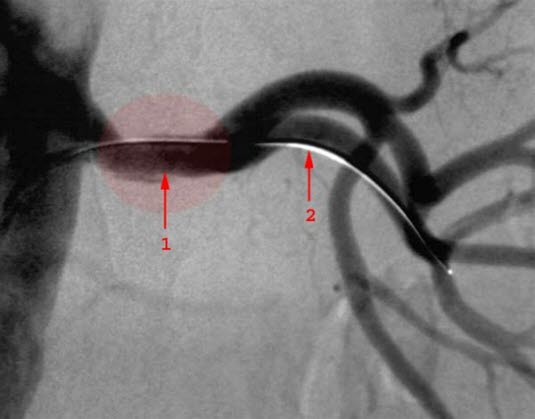

Venstre nyrearterie etter ballongdilatasjon

1. Dilatert stenose

2. Kateter